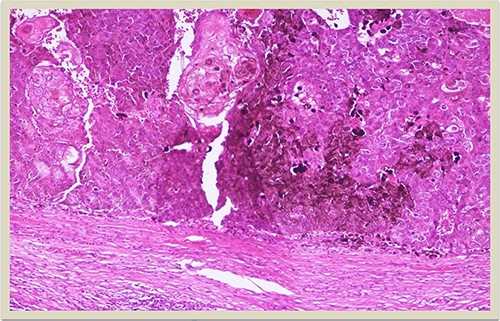

A 69-year-old man was admitted to our hospital with a nodular skin tumor of the back (Fig. 1). The patient had no ongologic history. We performed excisional biopsy that revealed collision tumor. The collision tumor consisted of mixed melanosquamous tumor (dermal squamomelanocytic tumor) together with BCC (Fig. 2). The BCC was superficial spreading. The mixed element contained squamous cell carcinoma of well/moderately differentiated and a neoplasm with melanotic characteristics, which due to cell atypia, presence of mitoses and high index of cell proliferation (Ki67: 80%) was described as melanoma (Fig. 3). Diagnosis of the melanotic and the squamous element was confirmed with immunohistochemistry (Figs 4 and 5).

H–E × 10: Higher magnification of the dermal squamomelanocytic tumor showing admixed malignant malanocytes and keratinizing squamous cell carcinoma cells (H–E stain ×10 magnification).